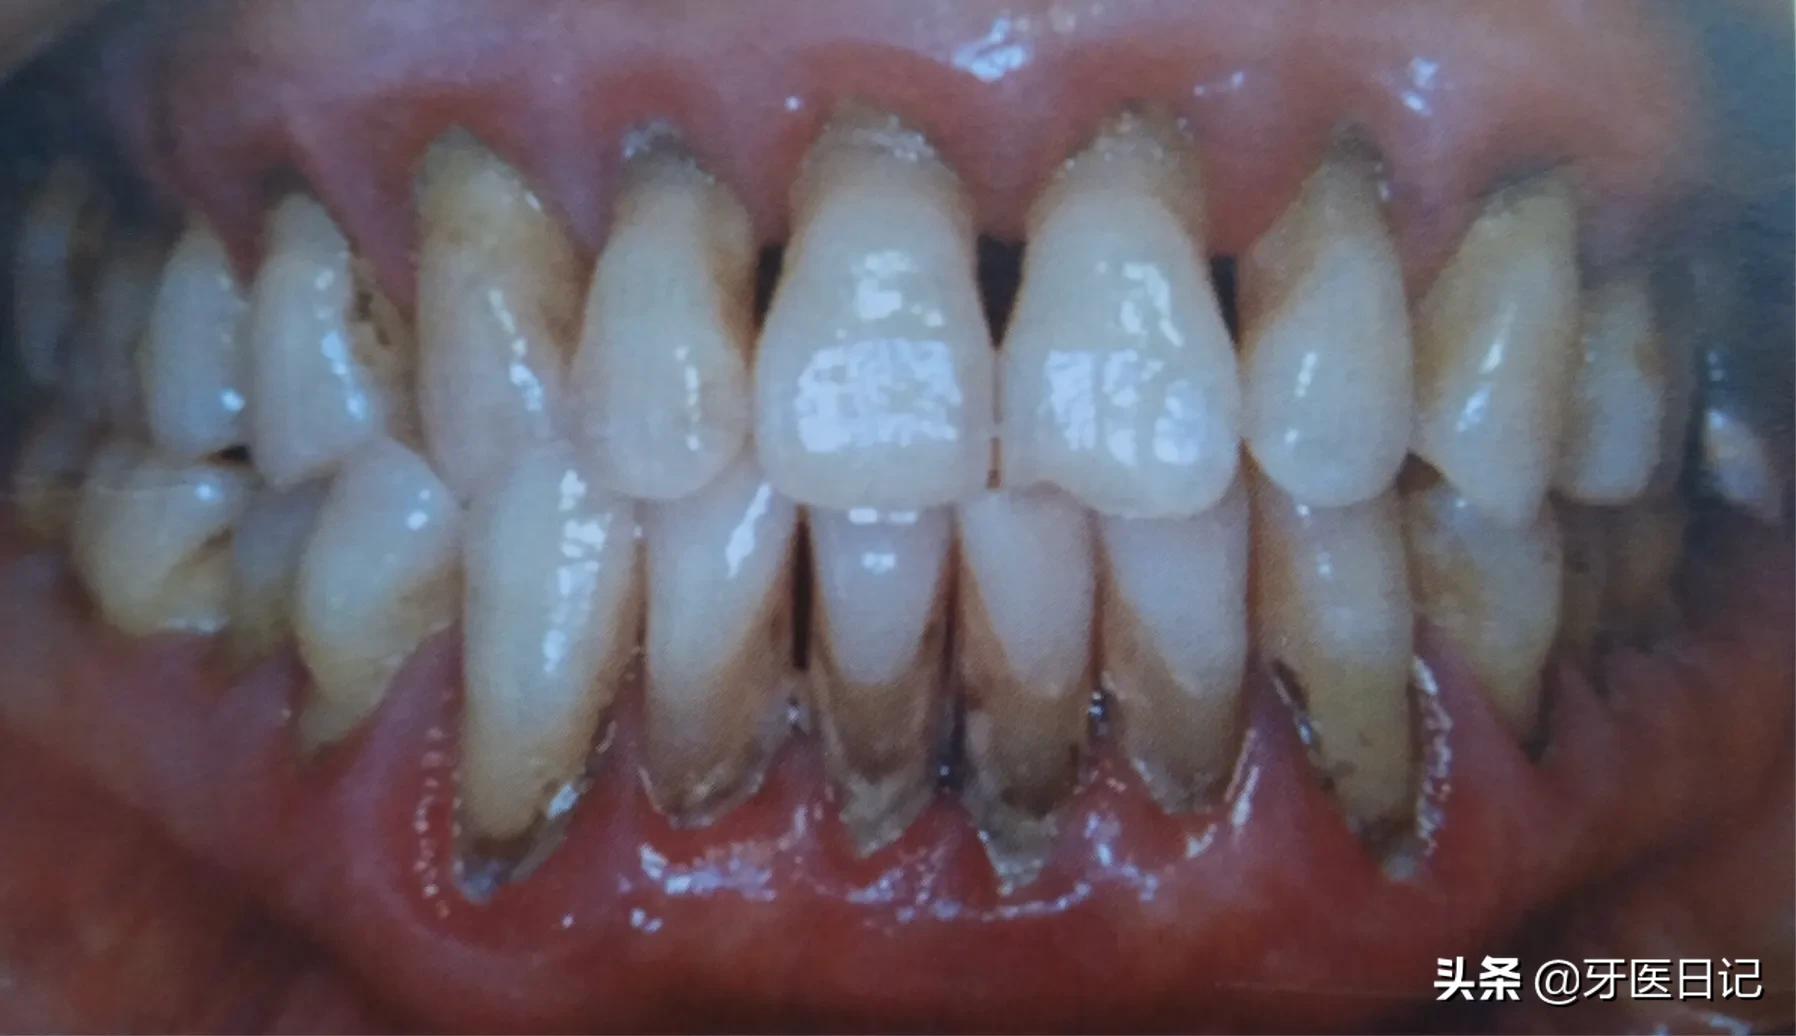

②牙周炎:主要表现牙齿的松动、移位,牙龈出血,牙槽骨的吸收,同时会伴有牙周袋溢脓口臭等表现

牙周炎如何形成的?

一部分牙龈炎的患者得不到及时治疗,炎症可向牙周深部发展,导致牙齿周围的支持丧失,比如牙齿周围的骨头,随着病变继续向牙根发展,逐渐出现牙齿松动移位,牙龈萎缩,急性肿胀疼痛。